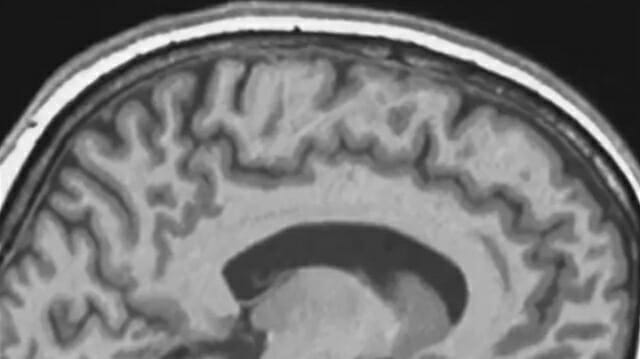

미국 매사추세츠공과대학(MIT) 레이첼 세이들러 교수 연구진은 장기 우주 비행이 인체 핵심 장기 중 하나인 뇌에 어떤 영향을 미치는지 확인하기 위해 우주비행사들의 자기공명영상(MRI) 촬영 데이터를 분석했다. 이번 연구 결과는 12일 미국 국립과학원회보(PNAS)에 발표됐다.

연구진은 우주 임무 전후 MRI 촬영 자료를 제공한 우주비행사 15명의 뇌 변화를 분석했다. 여기에 다른 우주비행사 11명의 기존 MRI 자료와, 미세중력 환경을 모사하기 위해 장기간 머리를 아래로 기울인 상태로 진행한 침상 안정(head-down tilt) 실험 참가자 24명의 데이터까지 종합해 비교했다.